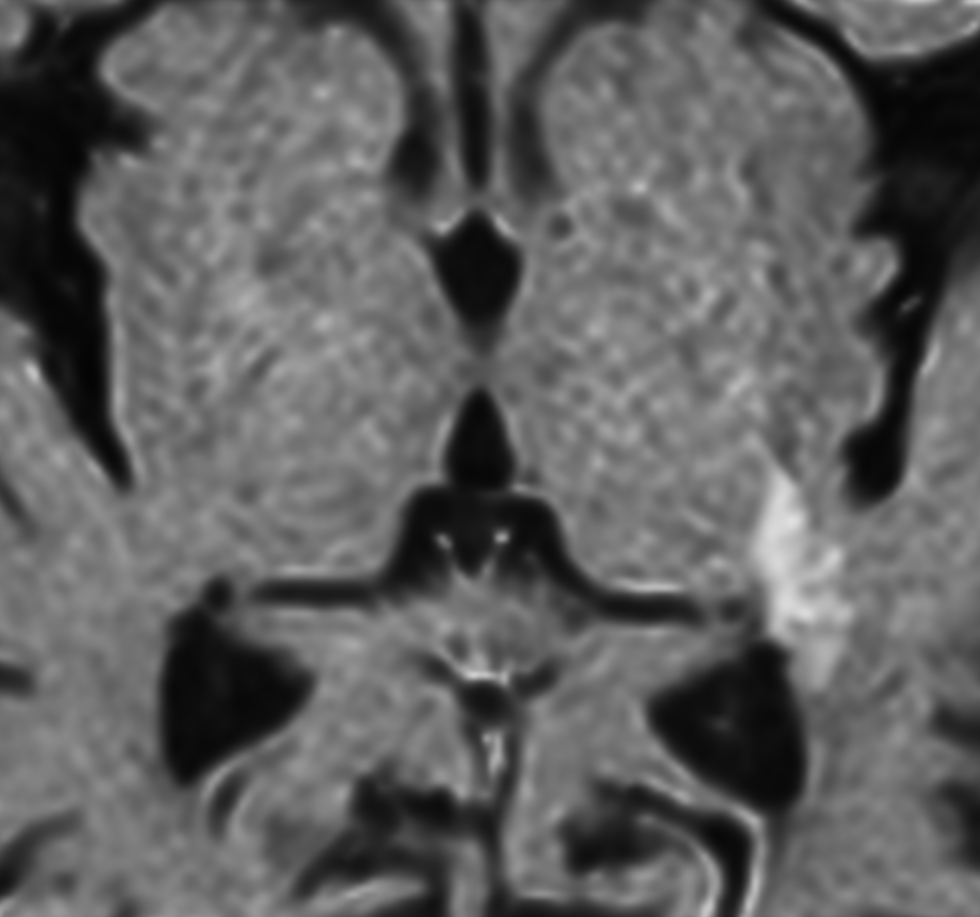

Zoom Diffusion (b1000)

-